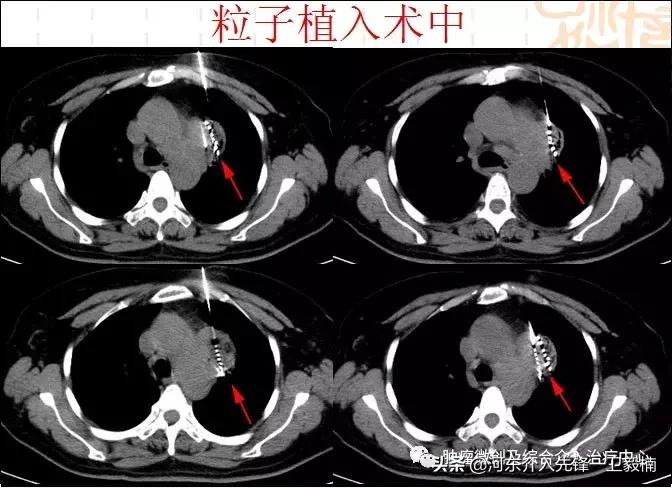

C:放射性粒子植入:此方法属于近距离放疗。有别于传统外放疗受正常组织耐受剂量限制的劣势,粒子植入通过穿刺针经皮肤穿进肿瘤内部,根据一定的原则及方法,将直径不到5mm的粒子均匀放置,每颗粒子都是一个放射源,它们在肿瘤内部24小时不间断对肿瘤进行照射。使瘤内剂量高,瘤外剂量很低。效果优于传统放射治疗。